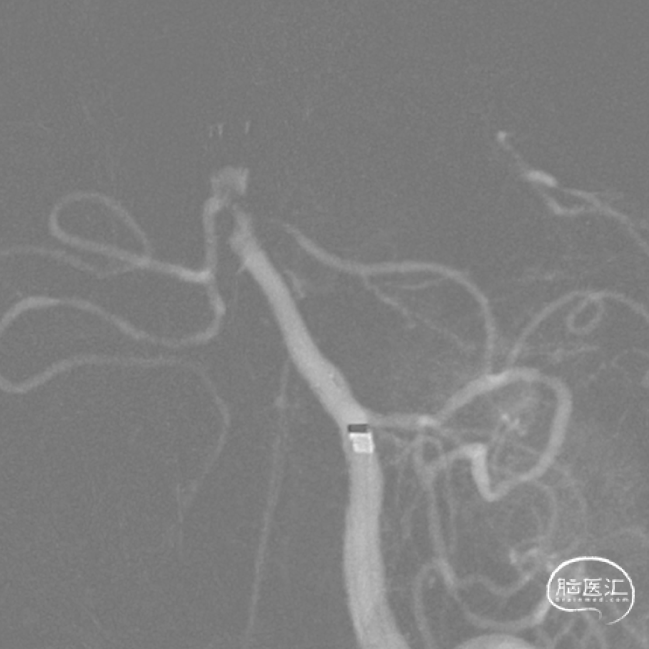

MRA

5.双侧椎-基底动脉、双侧大脑后动脉、右侧大脑前动脉闭塞;